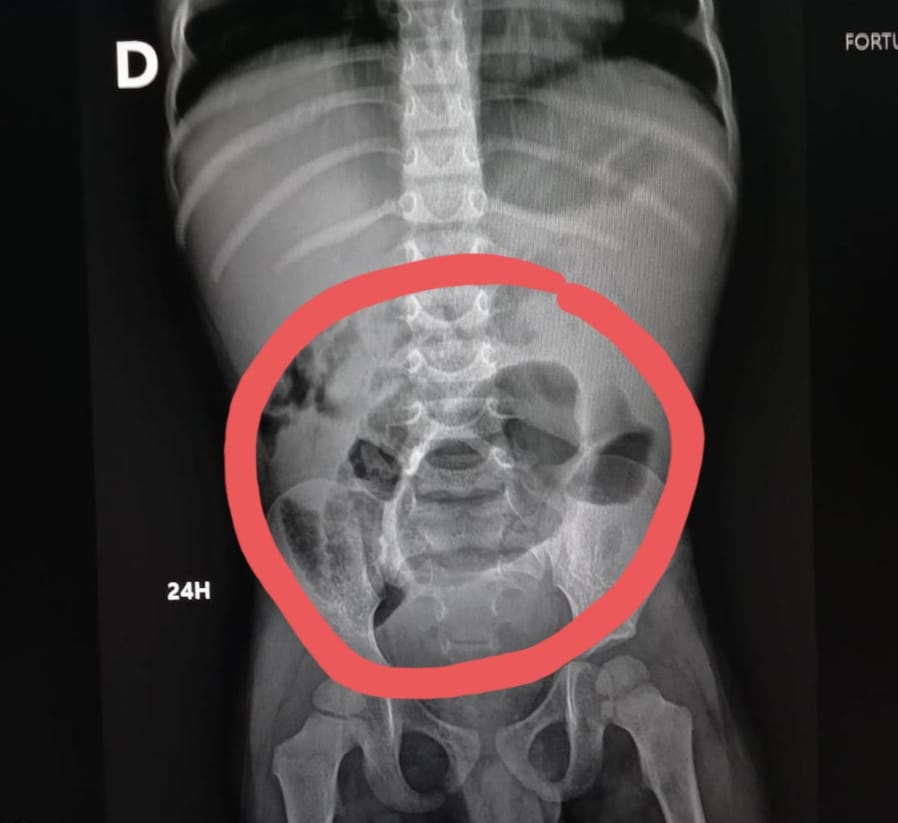

La doctora Idelsa Polanco encargada del departamento de gastroenterología del hospital pediátrico Hugo Mendoza explicó que el megacolon congénito también llamada Enfermedad de Hirschsprung es una ausencia de los ganglios nerviosos de la terminación del intestino, es decir el colon, cuya función es expulsar las heces fecales.

La especialista detalla que si no hay terminación, "la pupú se va acumulando en el colon y no hay quien la expulse hacia afuera y empieza a creer del tamaño de las heces fecales y se va quedando grande".

“La enfermedad se manifiesta en los primeros tres días del nacimiento el niño no evacúa, hace un taponamiento y hay que sacarle las heces fecales a través irrigaciones con algunos métodos", indicó la pediatra.

Otros síntomas en recién nacidos es el abdomen hinchado, vómitos frecuentes y estreñimiento o gases, que generan incomodidad en los bebés.

El doctor Elvyn Alcántara Encargado de la unidad colorrectal del hospital Robert Read dijo que se trata de un diagnóstico tardío porque durante 10 años asistido con supositorios de glicerina durante toda su vida para poder evacuar y precisamente ese es uno de los mayores signos de alarma.

"Mientras mayor tiempo, más el riesgo, hay niños que mueren de megacolon congénito no diagnosticado, si tu no puedes evacuar, tú te mueres, quizás por eso los padres desde los tiempos de antes ayudan a que el bebé pueda evacuar", narró el cirujano pediátrico.